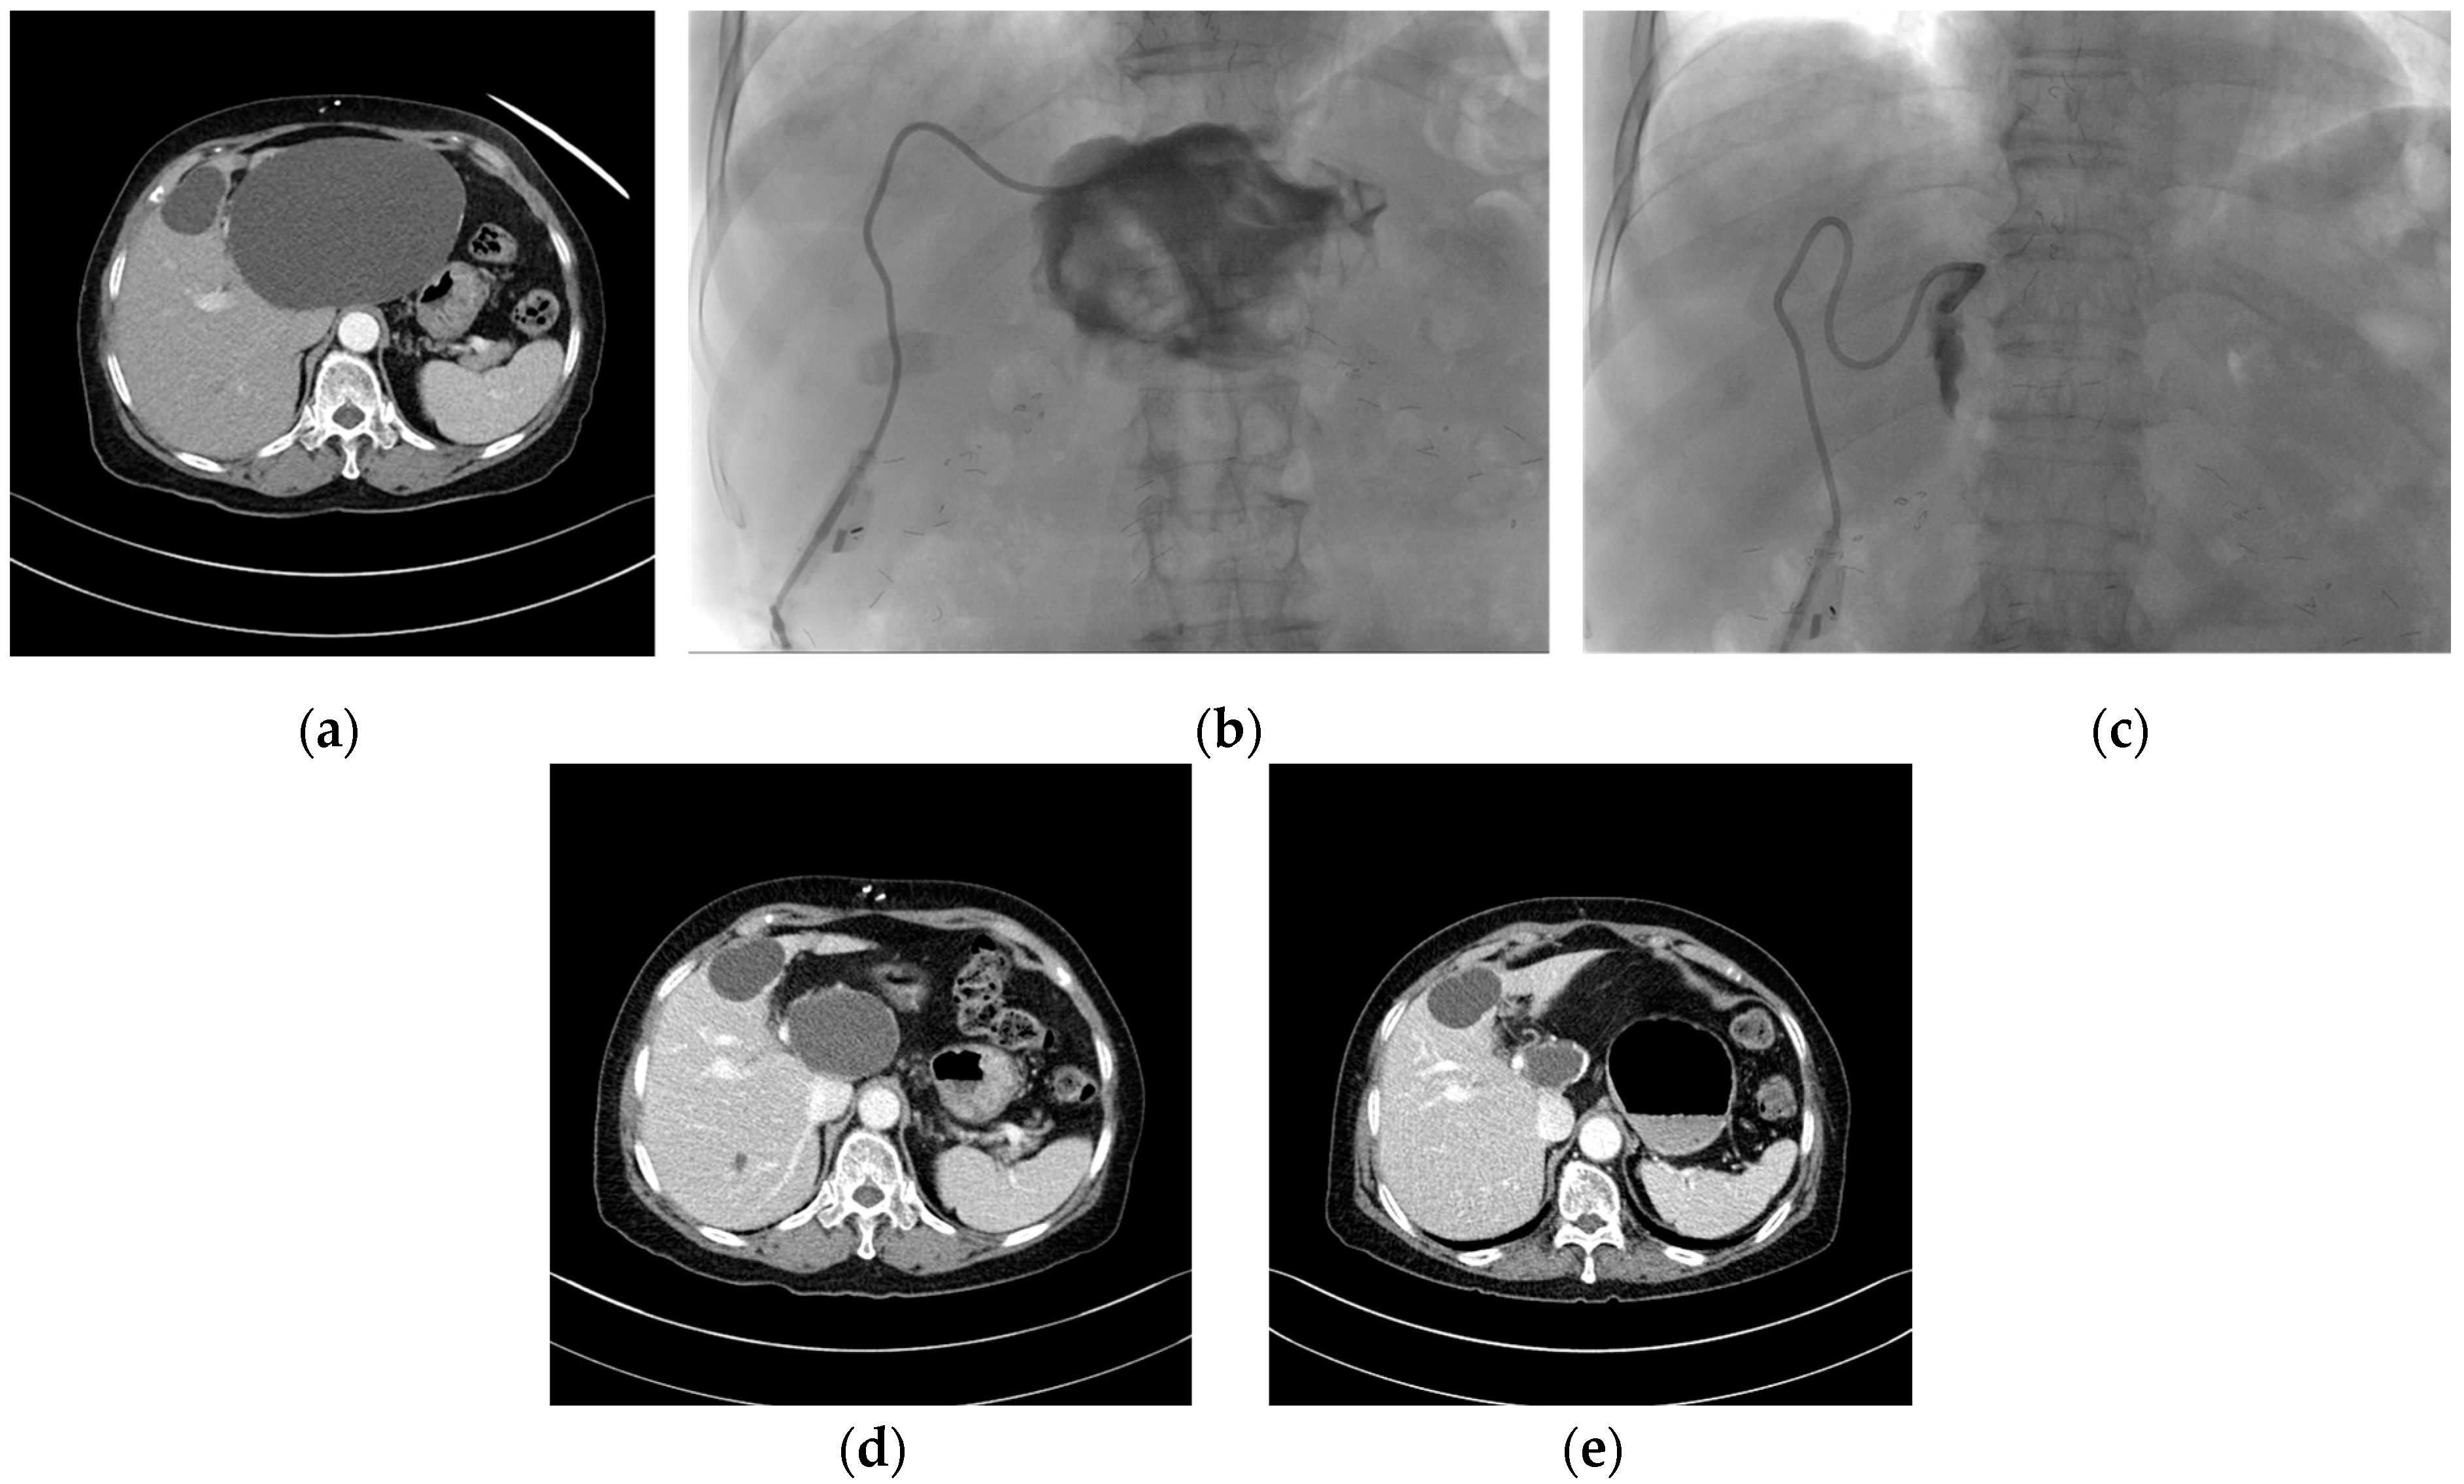

Incomplete treatment was carried out for patients who were very susceptible to alcohol or who developed severe alcohol intoxication symptoms such as abdominal pain or epilepsy. Incomplete treatment was defined as follows: (1) the exposure time of alcohol was insufficient; (2) the injected volume of alcohol was less than 10% of the aspirated cyst volume (Figure 1).

Figure 1. Case of incomplete alcohol sclerotherapy and natural course after treatment. (a) An enhanced CT scan performed on a 77-year-old woman presenting with early satiety revealed a large cyst measuring 14 × 10 × 13 cm maximum orthogonal cyst diameter in the left liver. The patient had a history of alcohol sensitivity. (b) After natural drainage of 1000 mL over the course of one day, tubography was performed. The cystic cavity was found to be collapsed, and contrast infusion and regurgitation proceeded smoothly. The planned injection of 100 mL of 99% alcohol was then initiated. However, at the time of injection of 40 mL, severe symptoms of alcohol intoxication manifested, which led to an immediate discontinuation of the injection and removal of the alcohol. (c) The next day, 18 mL of drainage was observed, so a second alcohol sclerotherapy was attempted, but severe pain occurred again when another 30 mL of alcohol was injected, so the alcohol was immediately removed. In the final tubography, the cystic cavity was found to be even more collapsed than before. Natural drainage was performed for 6 h, with minimal fluid drainage leading to the removal of the catheter. (d) CT scan performed after 6 months revealed the cystic cavity, measuring 6 × 5 × 6 cm in size. (e) CT scan performed after 12 months revealed that the size of the cyst was smaller (2 × 4 × 3 cm) without repeated sclerotherapy, and the cyst had shrunk to 96% of its pre-treatment size at 12 months.